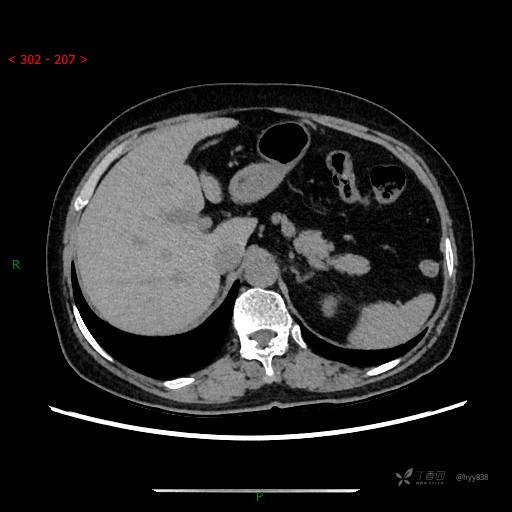

上腹部CT平扫